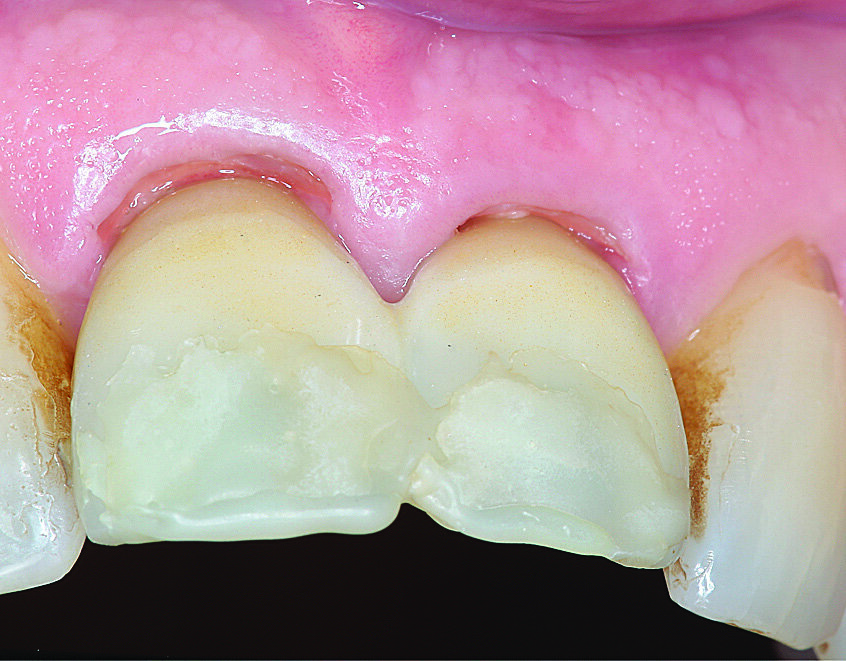

Dva mjeseca nakon implantacije uzet je otisak. Periimplantatno meko tkivo bilo je bez upale s lijepim izlaznim profilom. Fragment zuba jasno se vidi na pojedinačnoj rendgenskoj snimci, a razina interdentalne kosti i površina implantata ne ukazuju ni na kakve patološke promjene. Implantati su se stabilno oseointegrirali (Slika 10.). Otisak na implantatima uzet je materijalima Impregum™ (3M™ ESPE™), Permadyne™ (3M™ ESPE™) i individualnom žlicom za otiske. Kao definitivna opskrba dva mjeseca nakon implantacije izrađene su pojedinačne krunice od potpuno obložene cirkonij-oksidne keramike na titanijskim bazama (Slike 11. i 12.).

Slike 11 i 12. Definitivna protetska opskrba zubi 11 i 21: cirkonij-oksidne krunice na titanijskim bazama.